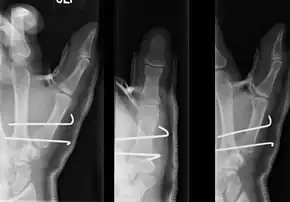

| Bennett fracture on x-ray | |

- For Bennett fractures where there is between 1 mm and 3 mm of displacement at the trapeziometacarpal joint, closed reduction and percutaneous pin fixation (CRPP) with Kirschner wires is often sufficient to ensure a satisfactory functional outcome. The wires are not employed to connect the two fracture fragments together, but rather to secure the first or second metacarpal to the trapezium.

- For Bennett fractures where there is more than 3 mm of displacement at the trapeziometacarpal joint, open reduction and internal fixation (ORIF) is typically recommended.